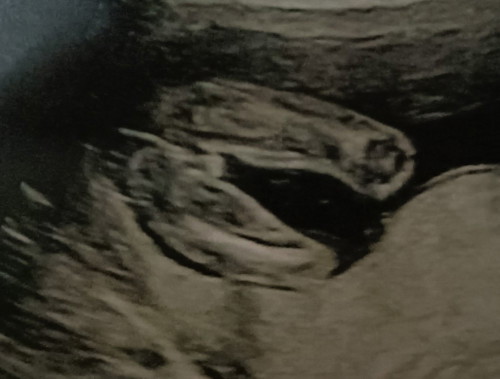

สอบถามจ้า แบบนี้เป็น ผู้ชายหรือหญิงครับ

สอยถามหน่อยครับ แบบนี้จะเป็นเด็กผู้ชายหรือหญิงครับ #ขอบคุณล่วงหน้าสำหรับความคิดเห็นค่ะ

น่าจะหญิงนะคะ ตอนเราอัลตราซาวตัวเล็กในท้องก็แบบนี้ ได้ลูกสาวค่ะ😅

ผู้หญิงรึเปล่าคะ เราได้ลูกชายเราเห็นชัดกว่านี้ค่ะ

ผู้ชายค่ะแม่ ขาสามขัดแจ๋ว555

น่าจะหญิงนะคะ เหมือนสายรกปิดไว้